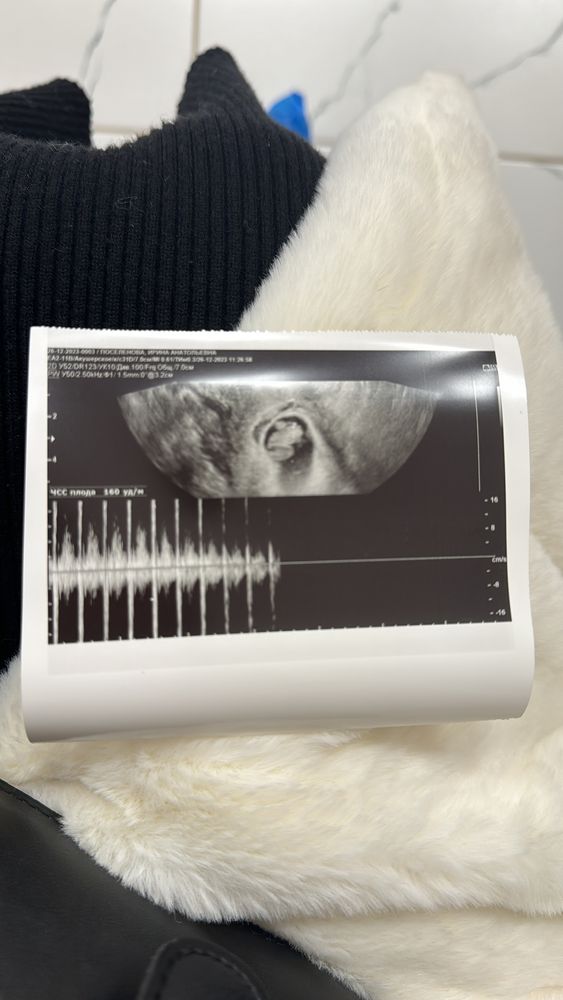

Страшно было идти на узи 8 недель

по узи все хорошо😁👍🏻 живет , развивается

В сентябре первая беременность закончилась выкидышем на 5 неделе, поэтому было страшно